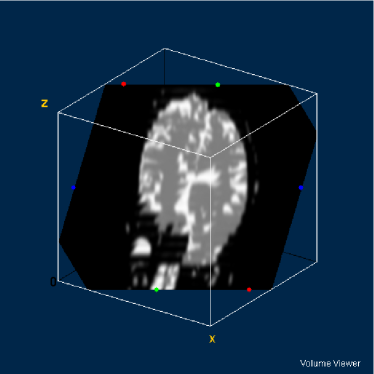

Refer to caption

Figure 4: DW-MR volume with diffusion exponent of 0 s/mm2

Figure 5: DW-MR volume with diffusion exponent of 500 s/mm2

Figure 6: DW-MR volume with diffusion exponent of 1000 s/mm2

The images can be considered as mathematical functions, where their domain is a region of the plain of the integers, called grid, and their counterdomain is the set of the possible values occupied by the pixels corresponding to each position of the grid.

Let fi:SW:subscript𝑓𝑖𝑆𝑊f_{i}:S\rightarrow W be the set of the diffusion-weighted MR images, where 1i31𝑖31\leq i\leq 3, SZ2𝑆superscriptZ2S\subseteq\textbf{Z}^{2} is the grid of the image fisubscript𝑓𝑖f_{i}, where WR𝑊RW\subseteq\textbf{R} is its counterdomain. The synthetic multispectral image f:SW3:𝑓𝑆superscript𝑊3f:S\rightarrow W^{3} corresponding to a determined slice of the volume composed by the DW-MR volumes presented in figures 4, 5 and 4 is given by: